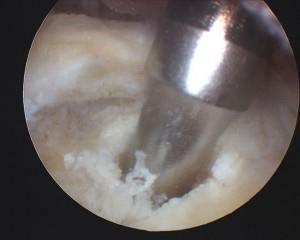

Anchor placed in bone

Sutures placed in tendon